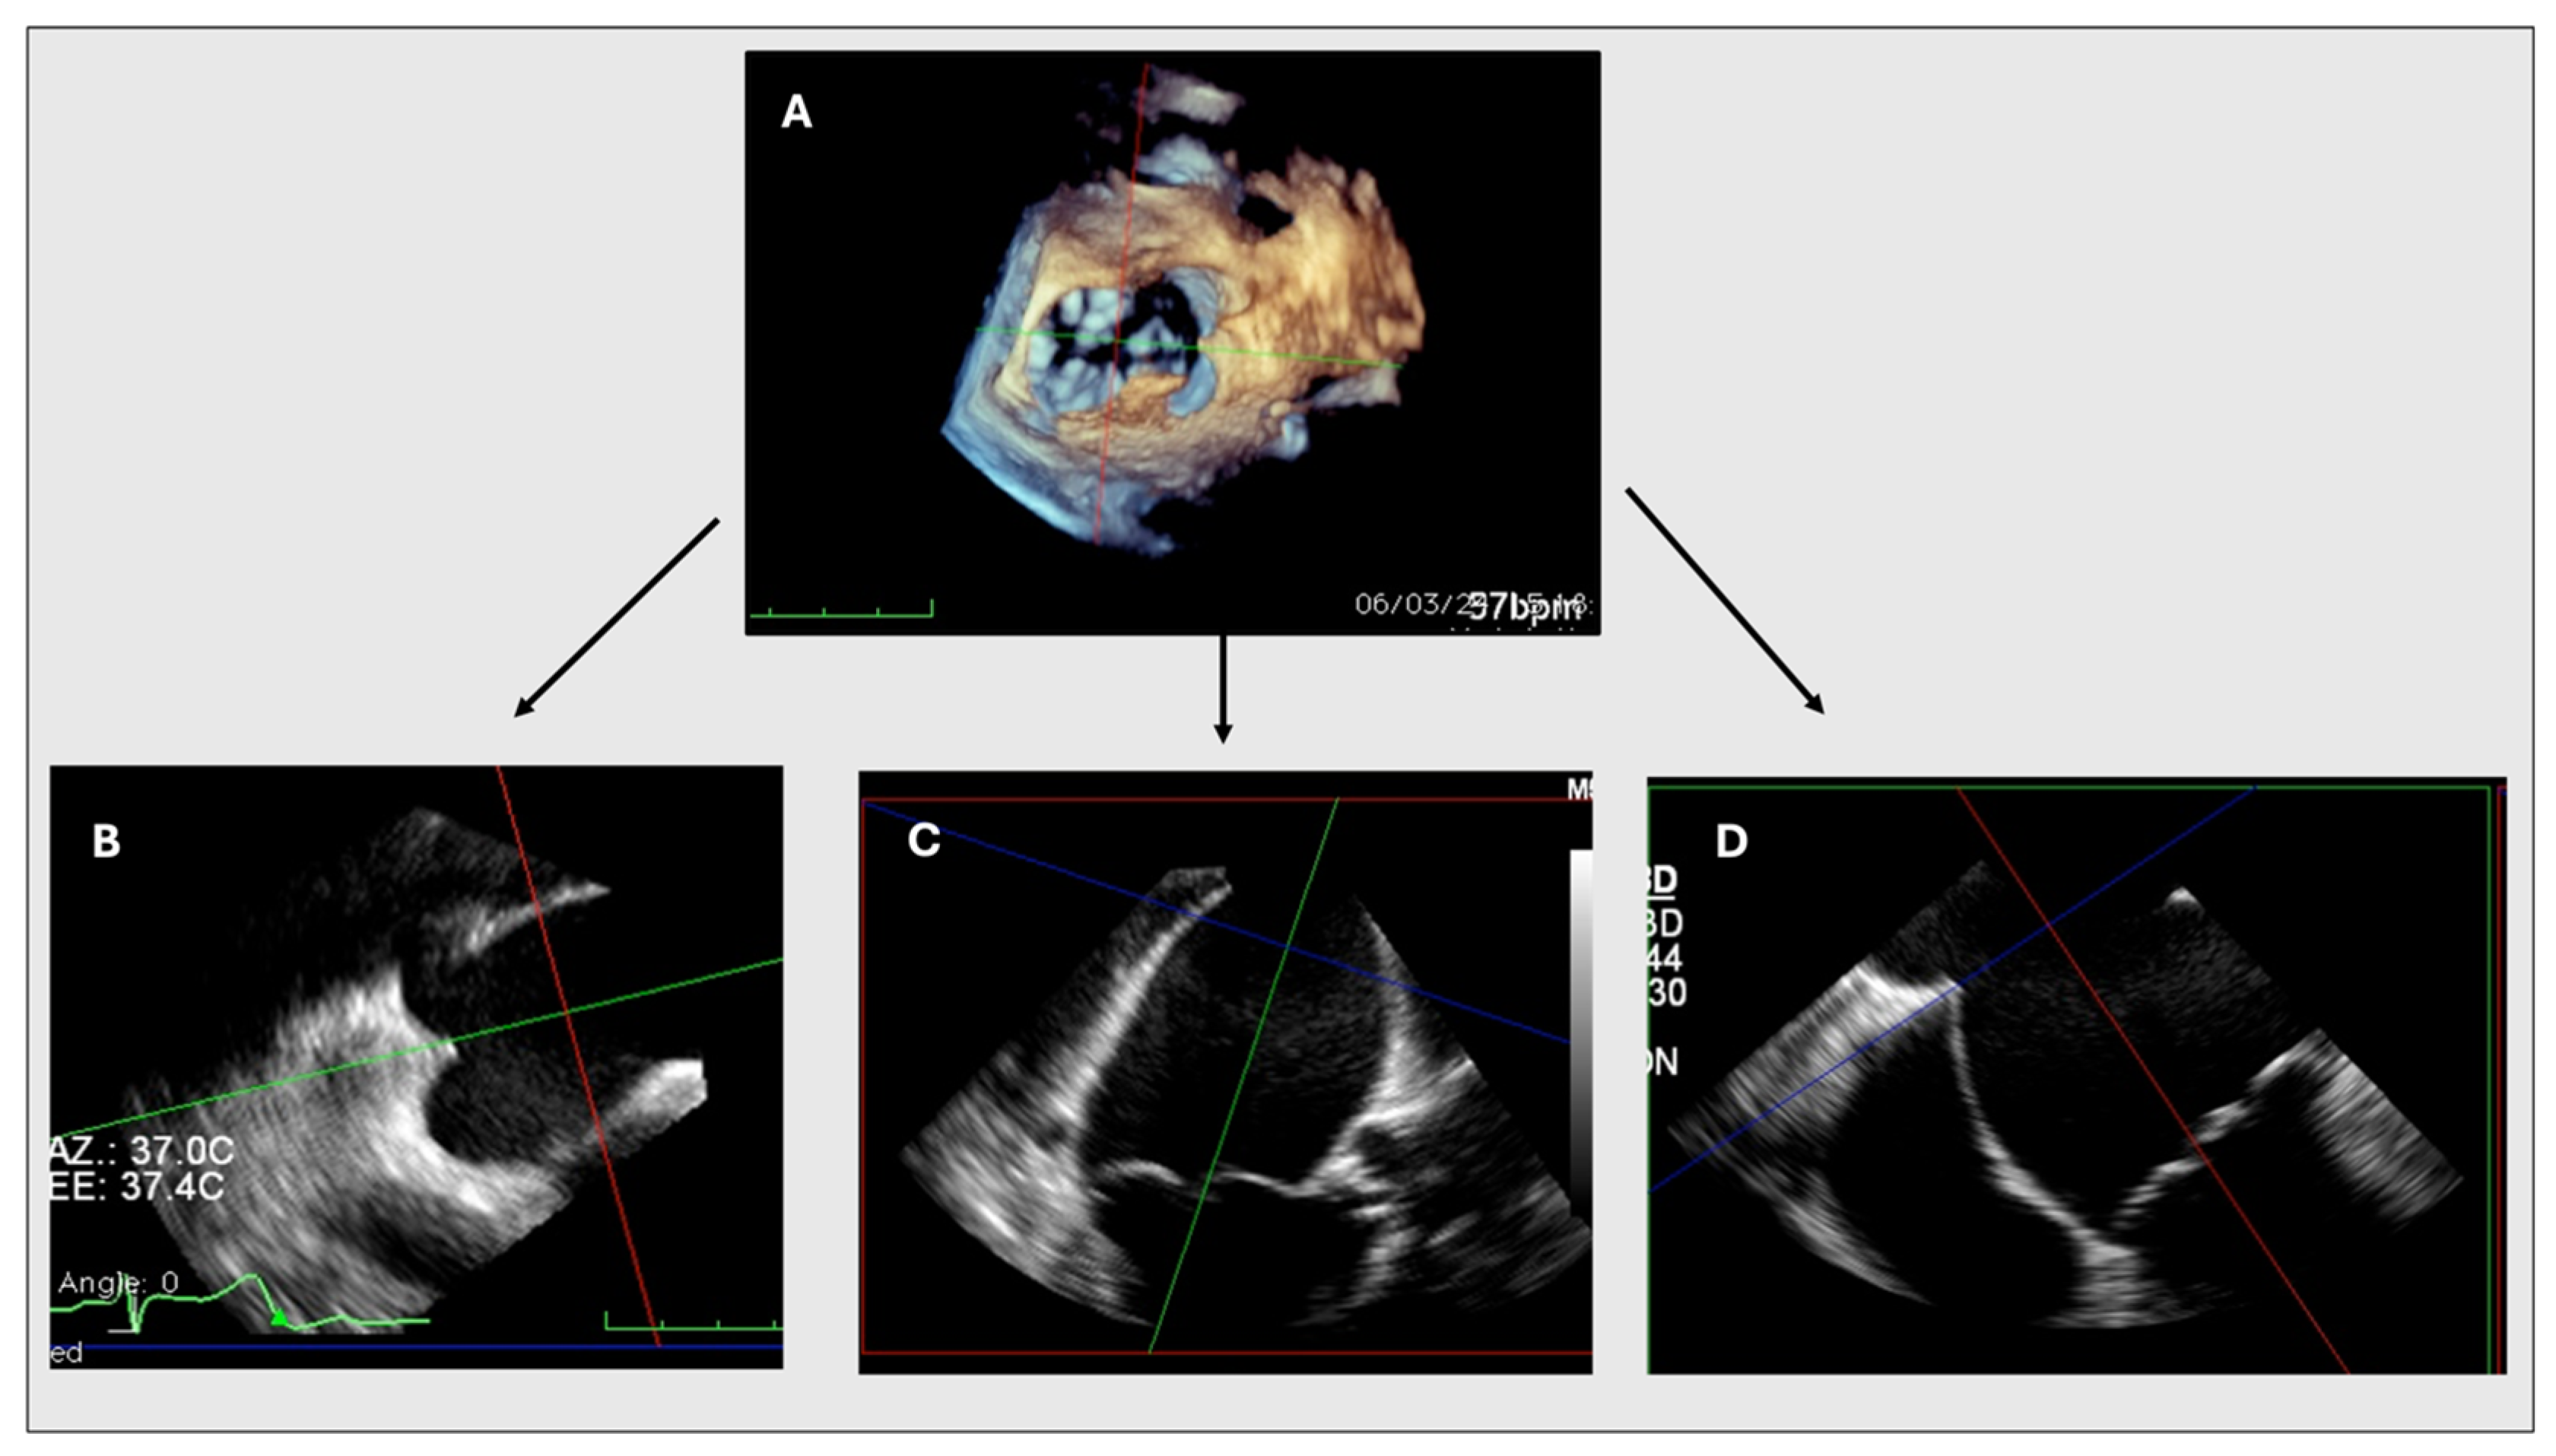

2.2. MPR Method